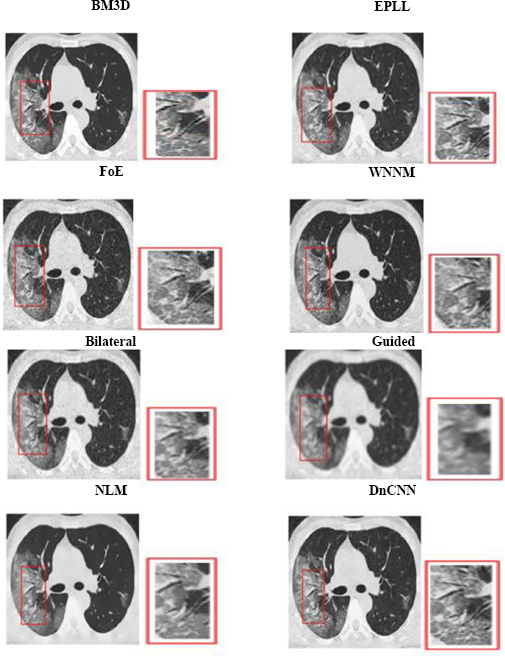

Fig. (4) shows the results at a noise variance of 0.01, where it has been observed that all algorithms produce clear images, except for the Guided algorithm.

Fig. (5) shows the results at a noise variance of 0.05, where it has been observed that the BM3D, EPLL, and WNNM algorithms produce clearer images compared to other algorithms. NLM and DnCNN also perform well, but not as well as the above-mentioned three algorithms.

Fig. (4).

The output of different algorithms at a noise variance of 0.01.

Fig. (5).

The output of different algorithms at a noise variance of 0.05.

Fig. (6) shows the results at a noise variance of 0.09, where it is observed that the BM3D, EPLL, and WNNM algorithms produce clearer images compared to other algorithms. Another algorithm, DnCNN, also performs well, but not so well as the above-mentioned three algorithms.

Fig. (6).

The output of different algorithms at noise variance 0.09.

Fig. (7) shows the results at a noise variance of 0.5, where it has been observed that all the algorithms produce blurred images, except for the BM3D algorithm. However, the results of the BM3D algorithm are not so satisfactory. As a result, it has been observed that at a noise variance of 0.5, none of the algorithms performed well.

Fig. (7).

The output of different algorithms at Noise Variance 0.50.

4.2. Visual Analysis

Visual analysis of the usual MRI and HRCT images is used to examine the qualitative performance of each denoising algorithm. Special attention was paid to anatomically relevant sites, such as fine pulmonary textures in HRCT and gray-white matter boundaries in T1-weighted brain MRI.

The visual quality of the denoised images was determined on cropped and zoomed regions of interest (ROIs). The capability of the algorithms to minimize noise while preserving the most essential features, such as tumor borders, ventricular boundaries, or alveolar boundaries, was tested. Such an analysis is crucial, especially in medical imaging, where even slight degradation or excessive smoothing may obscure diagnostic clues. Perceived quality and artifact suppression are illuminated by visual comparisons, and quantitative measurements are corroborated.